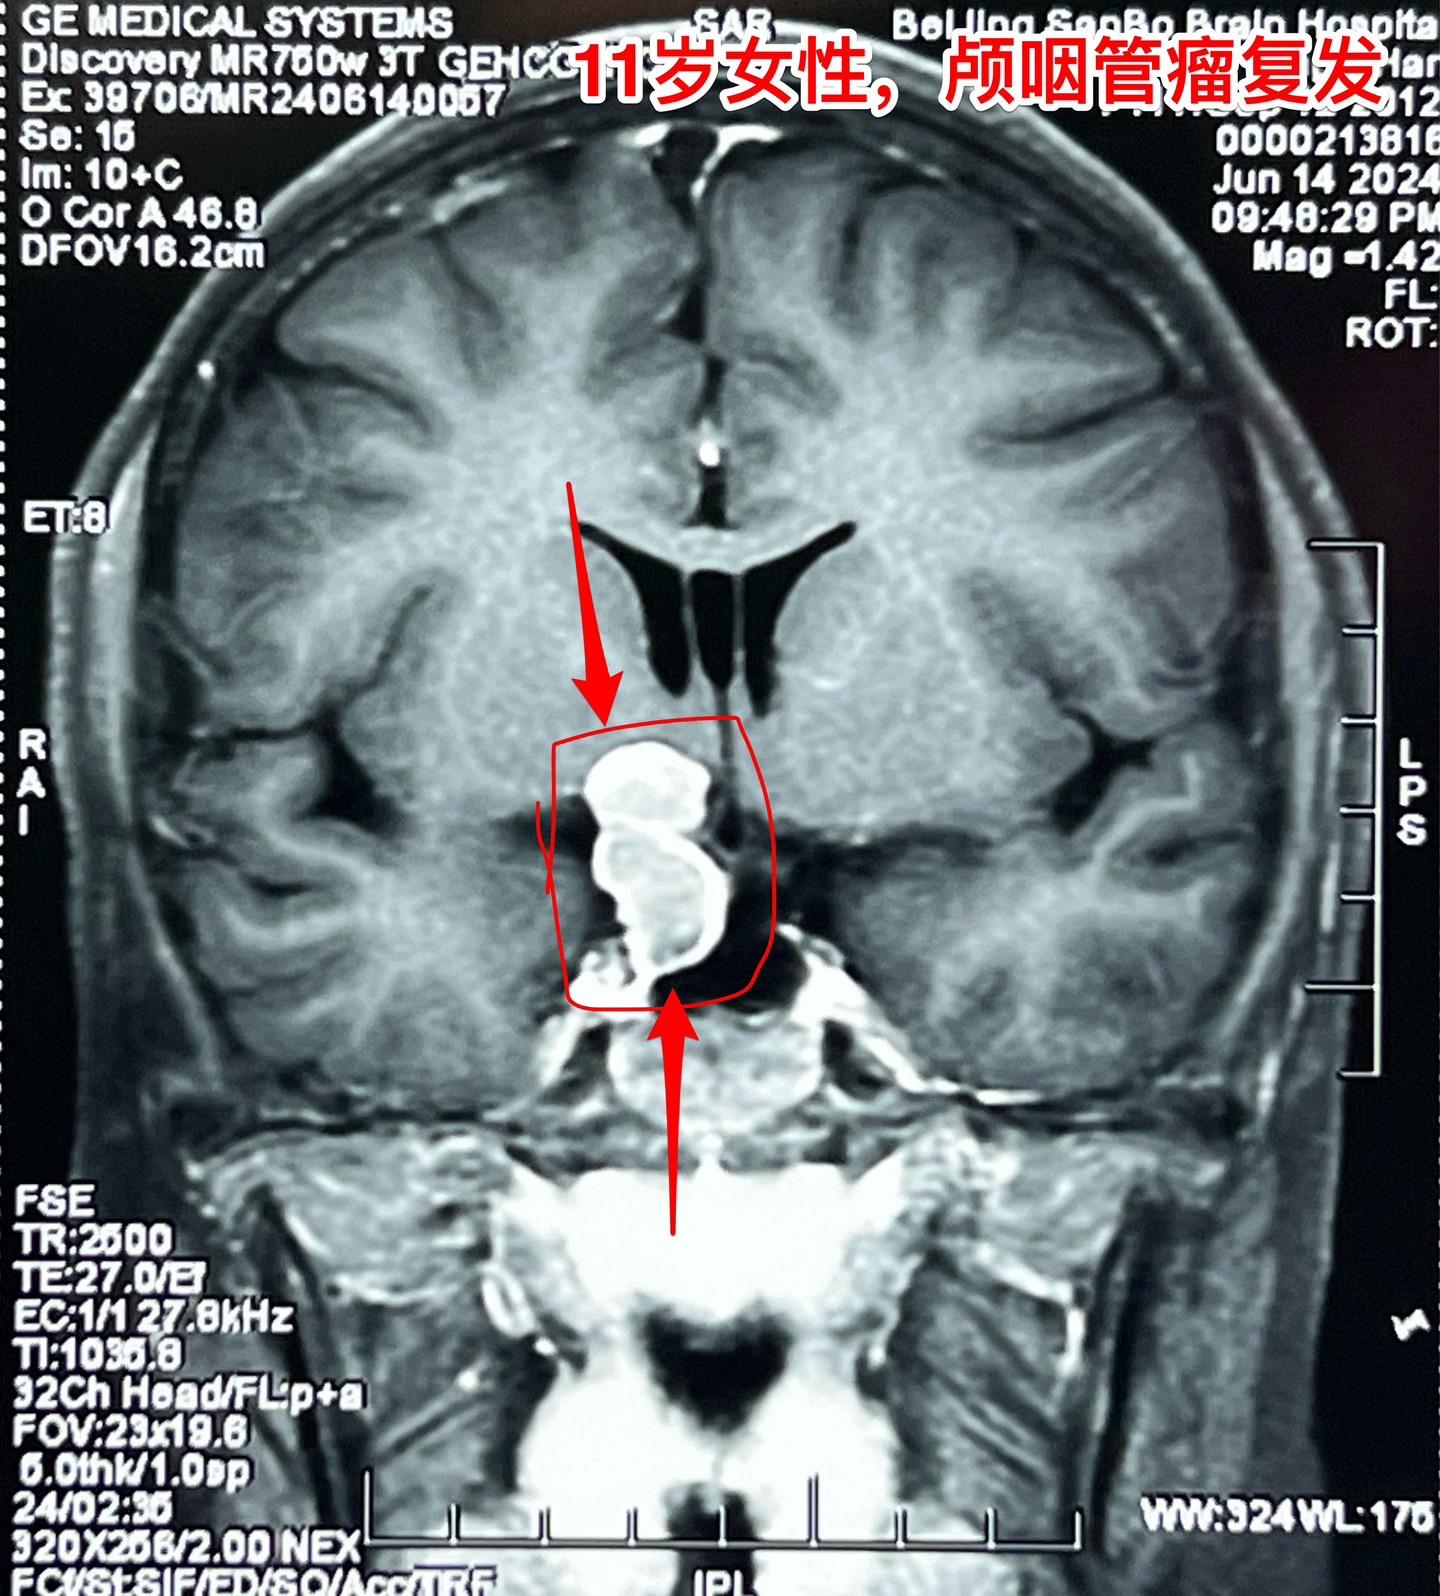

颅咽管瘤复发,病人该如何面对?11岁四川女孩子,颅咽管瘤复发了! 距离第一次经鼻内镜手术不到一年时间,颅咽管瘤就复发了,右眼视力下降。所以只能再次手术 近3年时间内我们科遇到的经鼻手术后复发的颅咽管瘤病例数呈显著增长趋势。在2024年完成的90例颅咽管瘤中,经鼻手术后复发者占比为12.2%。 这个增长趋势与近年来中国开展经鼻内镜手术切除颅咽管瘤例数的增长趋势是一致的。 4月21日我们作了开颅手术,将肿瘤完全切除了。 颅咽管瘤是神经外